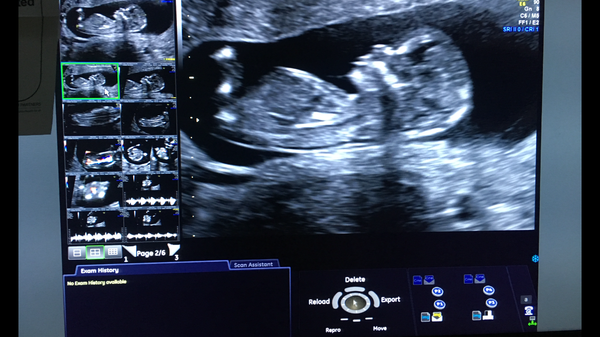

@AssumeItWasSomethingClever Lovely scan! I can’t see a nub so not sure on the sex. How far are you?

@AssumeItWasSomethingClever what a lovely scan of baby such clear features! I'm not great at guesses but looks girly unless the nub rises. So glad you enjoyed your hen weekend and you were able to tell everyone. You have a lot of exciting times ahead!

Just back from scan - all fine! So relieved. Risk of downs 1:2000, amazing relief after last time. We are so happy! Now to celebrate with a long day at work ;-)

Oh and I’m now measuring 13 weeks and EDD 27.03.19

Lovely scan photo @Nightmanagerfan

lovely scans @assumeitwassomethingclever (what an ace little profile it has!) and @nightmanagerfan. So pleased all's looking good.